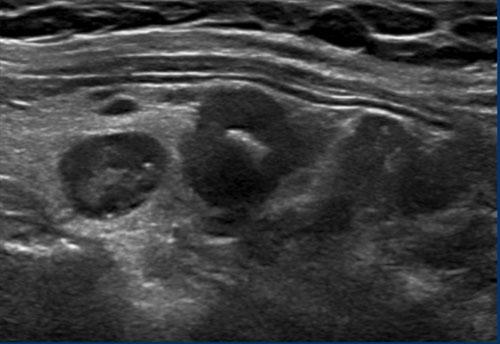

Trường hợp 3

Quan sát hình ảnh và xác định điểm TI-RADS.

Cuộn hình ảnh để xem điểm TI-RADS.

Lưu ý các tiêu điểm tăng âm nhỏ hiện diện.

Tổng cộng 6 điểm tương ứng với điểm TI-RADS là 4.